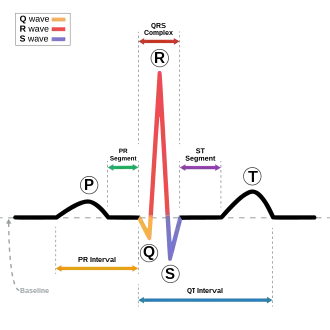

Schematic representation of a normal sinus rhythm EKG wave

In electrocardiography, the PR interval is the period, measured in milliseconds, that extends from the beginning of the P wave (the onset of atrial depolarization) until the beginning of the QRS complex (the onset of ventricular depolarization); it is normally between 120 and 200 ms in duration. The PR interval is sometimes termed the PQ interval.